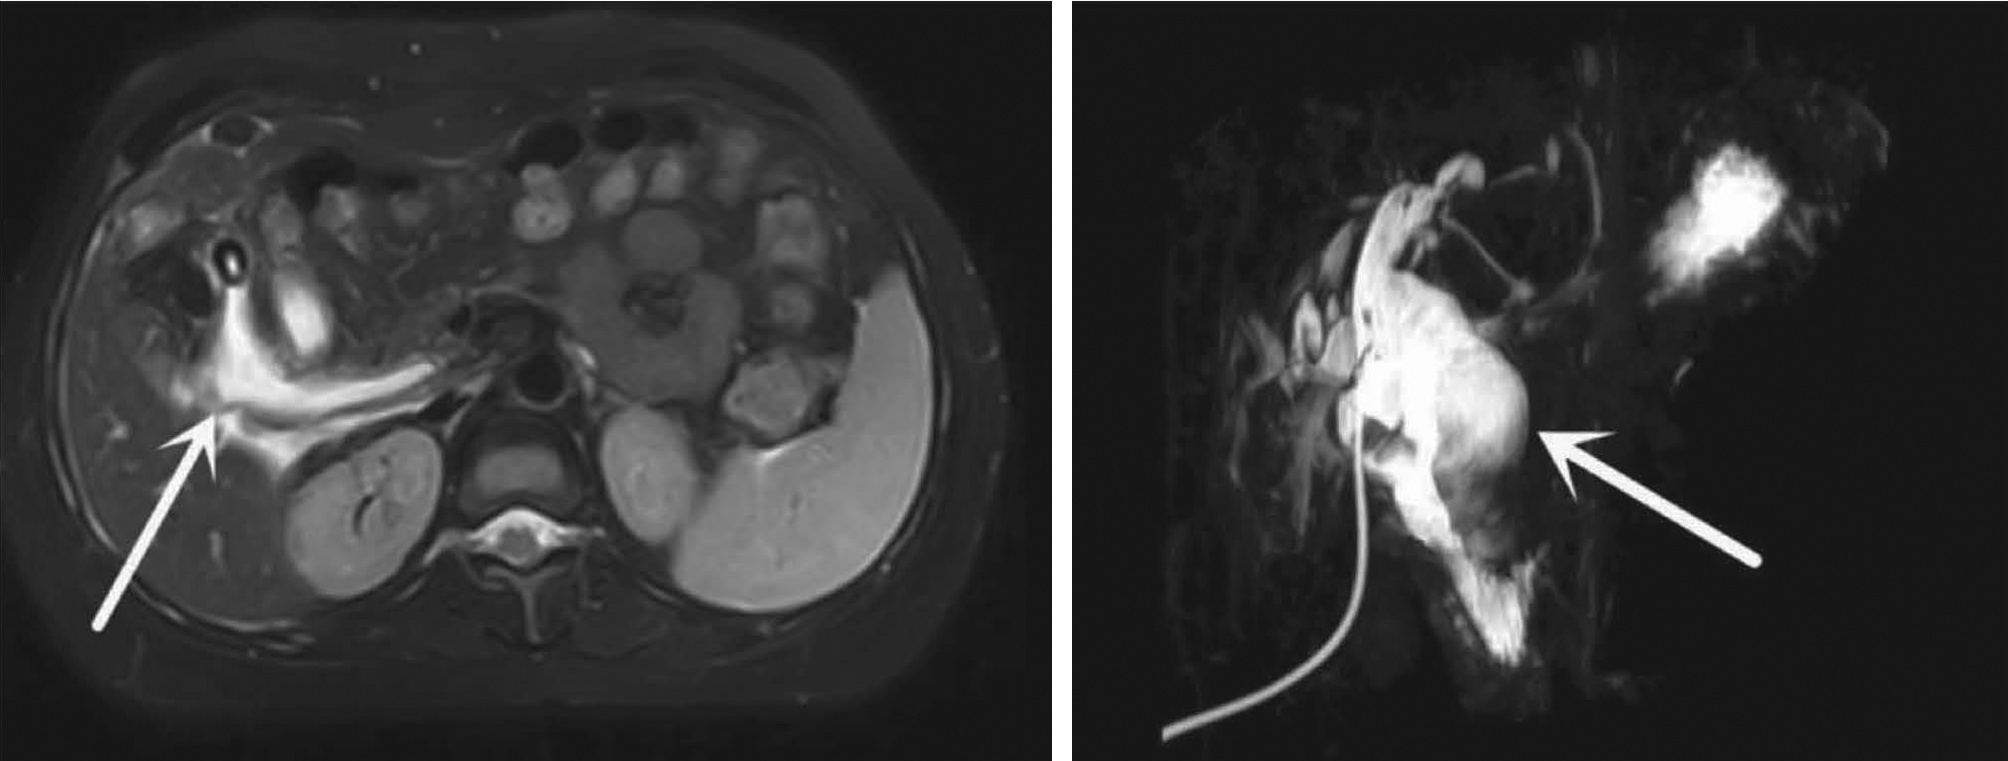

IgG4相关腹膜后纤维化1例报告

李朝霞, 刘洋, 李楠, 纪竹慧, 辛桂杰

2022, 38(5): 1126-1128. DOI: 10.3969/j.issn.1001-5256.2022.05.030

摘要(876) HTML (399) PDF (2161KB)(74)

摘要: